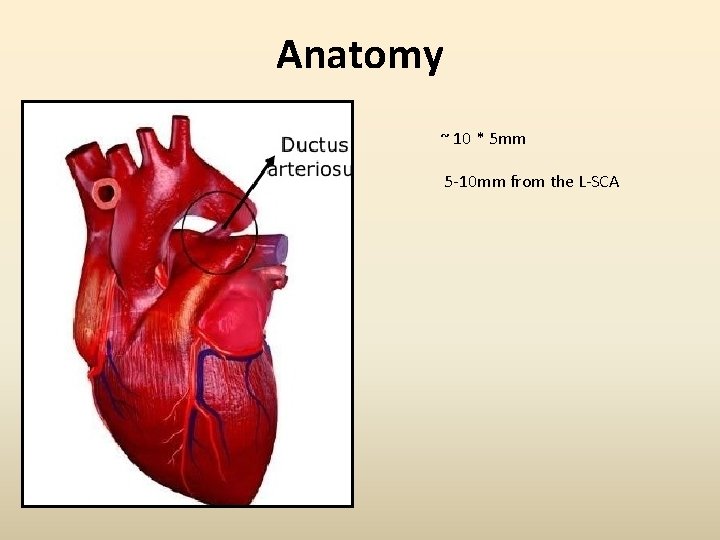

Anatomy ~ 10 * 5 mm 5 -10 mm from the L-SCA